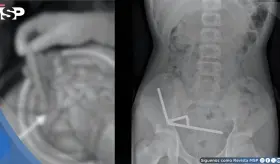

Las imágenes sugirieron un tumor con hueso, grasa y tejido cerebral dentro del recto, confirmando un diagnóstico poco común que solo se documenta en uno de cada 35.000 a 40.000 casos a nivel mundial.